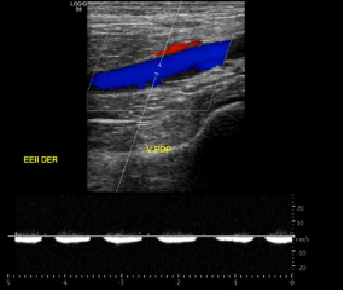

Desgarro Músculos gastrocnemios como hallazgo incidental en ecografía Doppler venoso EEII Der.

Paciente femenino de 34 años de edad. Orden medica con diagnóstico de contractura muscular y observación de TVP, se pide ecografía Doppler de pierna der (EEII inf DER).

Paciente con sintomatología de dolor intenso en pierna derecha en la región posterior después de bajar del bus, no indica temporalidad ni otros cambios. .

Se realiza protocolo por TVP. Paciente semisentado.

Sistema venoso superficial y profundo permeable y compresible sin signos de trombosis.

Incidentalmente, extenso desgarro miofascial total del gastrocnemio medial asociado a gran hematoma organizado interfascial. Desgarro miofascial del musculo gastrocnemio lateral.